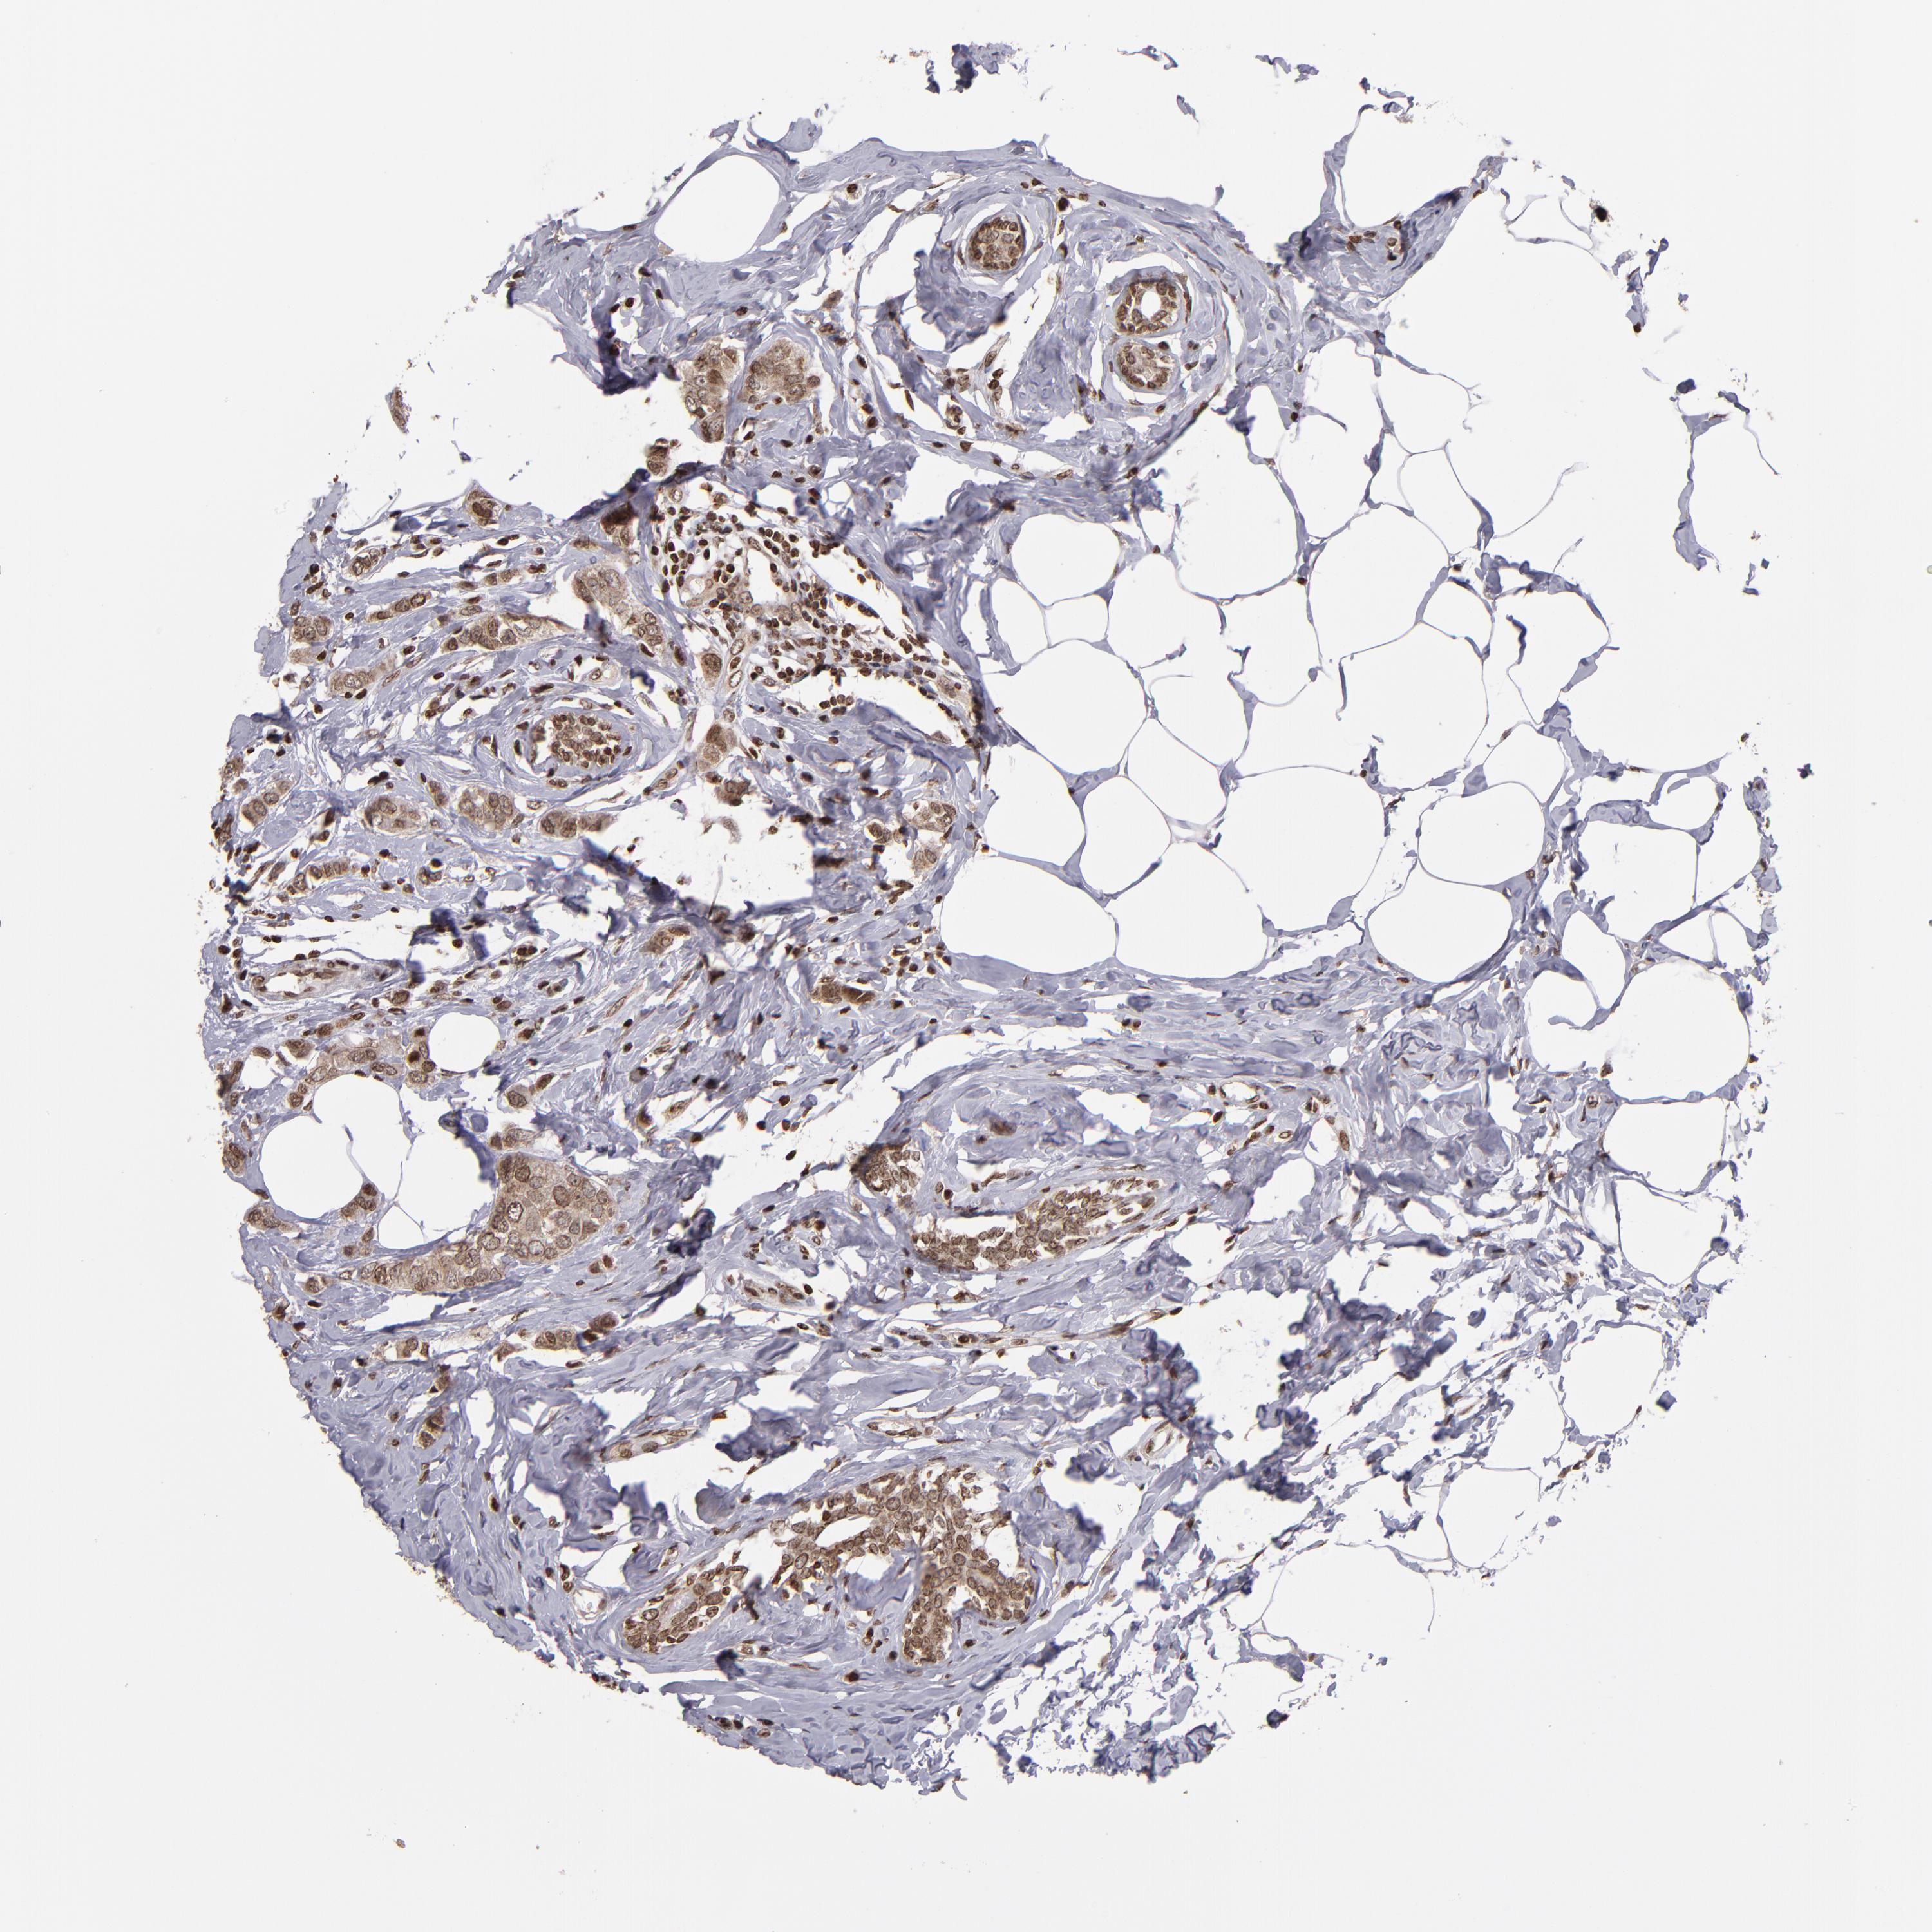

CANCER BREAST CANCER Show tissue menu

BRCA TCGA BRCA VALIDATION PROTEIN EXPRESSION

ANTIBODIES

AND

VALIDATION